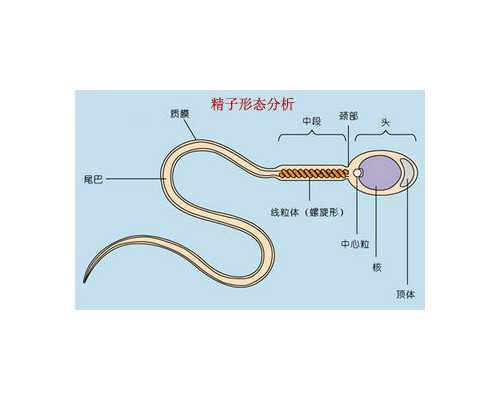

夫妻雙方的檢查主要是檢查夫妻雙方的生殖系統(tǒng),檢查內(nèi)容包括夫妻雙方的身體狀況和體內(nèi)激素水平,以判斷排卵、受精及受精后胚胎的發(fā)育情況。具體來說,夫妻雙方的檢查包括:男方檢查,主要是檢查精子質(zhì)量;女方檢查,主要是檢查卵子質(zhì)量和宮腔環(huán)境。此外,夫妻雙方還應(yīng)定期進行抗體檢查,以確保安全,同時還要檢查男方的精液,以確保精子的活力和數(shù)量。